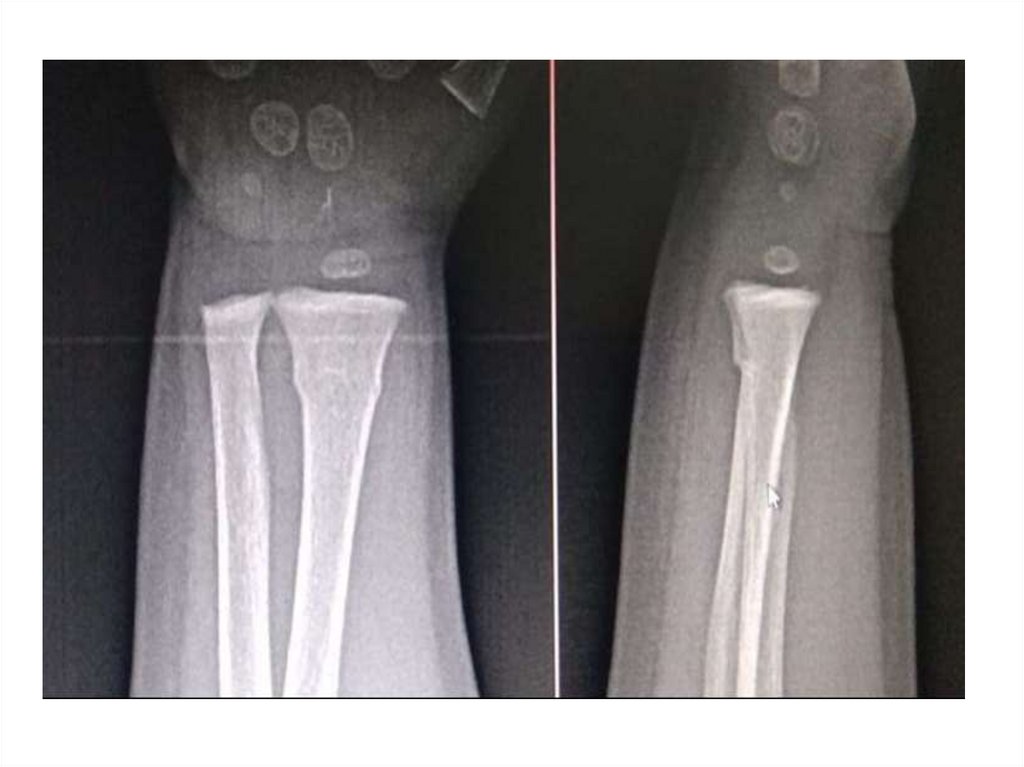

Назовите

• Вид исследования

• Область исследования

• Патологию